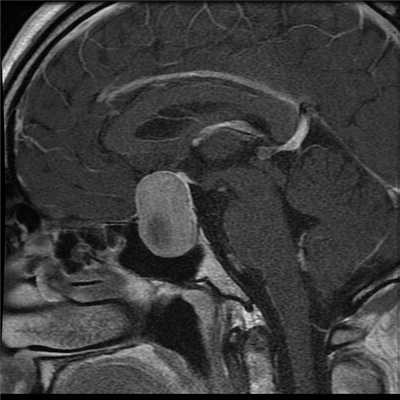

МРТ гипофиза при краниофарингиоме: сканы в разных проекциях

Магнитно-резонансная томография - один из высокоинформативных способов инструментальной диагностики. Исследование показывает мельчайшие изменения в структуре органов, предположительный характер патологии, взаимоотношение с близлежащими структурами. Скульптурирование многоплоскостных изображений во время МР-сканирования подразумевает использование принципа ядерно-магнитного резонанса, но не рентгеновских лучей. Атомы водорода в клетках воды, попав в поле, генерируемое аппаратом, начинают перестраиваться, при обретении привычного положения выделяется определенное количество энергии, которое фиксируют датчики, а обрабатывает компьютерная программа. Какого-либо вредоносного воздействия на организм во время диагностической процедуры нет, при условии отсутствия в теле металлических составляющих. Врач получает возможность рассматривать патологический очаг в любой плоскости, что невозможно при обычной рентгенографии или КТ.